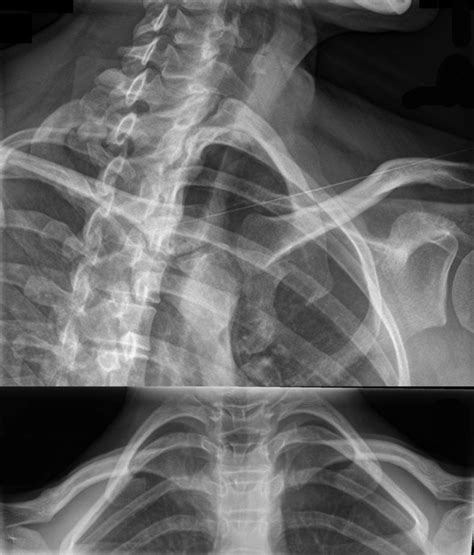

Diagnostic procedures for sternal costal joint issues may include:

• Physical Examination: A healthcare professional will examine the chest area for tenderness, swelling, and any signs of injury. They may also assess the range of motion and any pain during movement.

• Medical History: The patient's medical history, including any recent injuries or illnesses, will be reviewed to identify potential causes of the symptoms.

• Imaging Tests: X-rays, CT scans, or MRI scans may be used to visualize the sternal costal joints and surrounding structures. These tests can help identify fractures, inflammation, or other abnormalities.